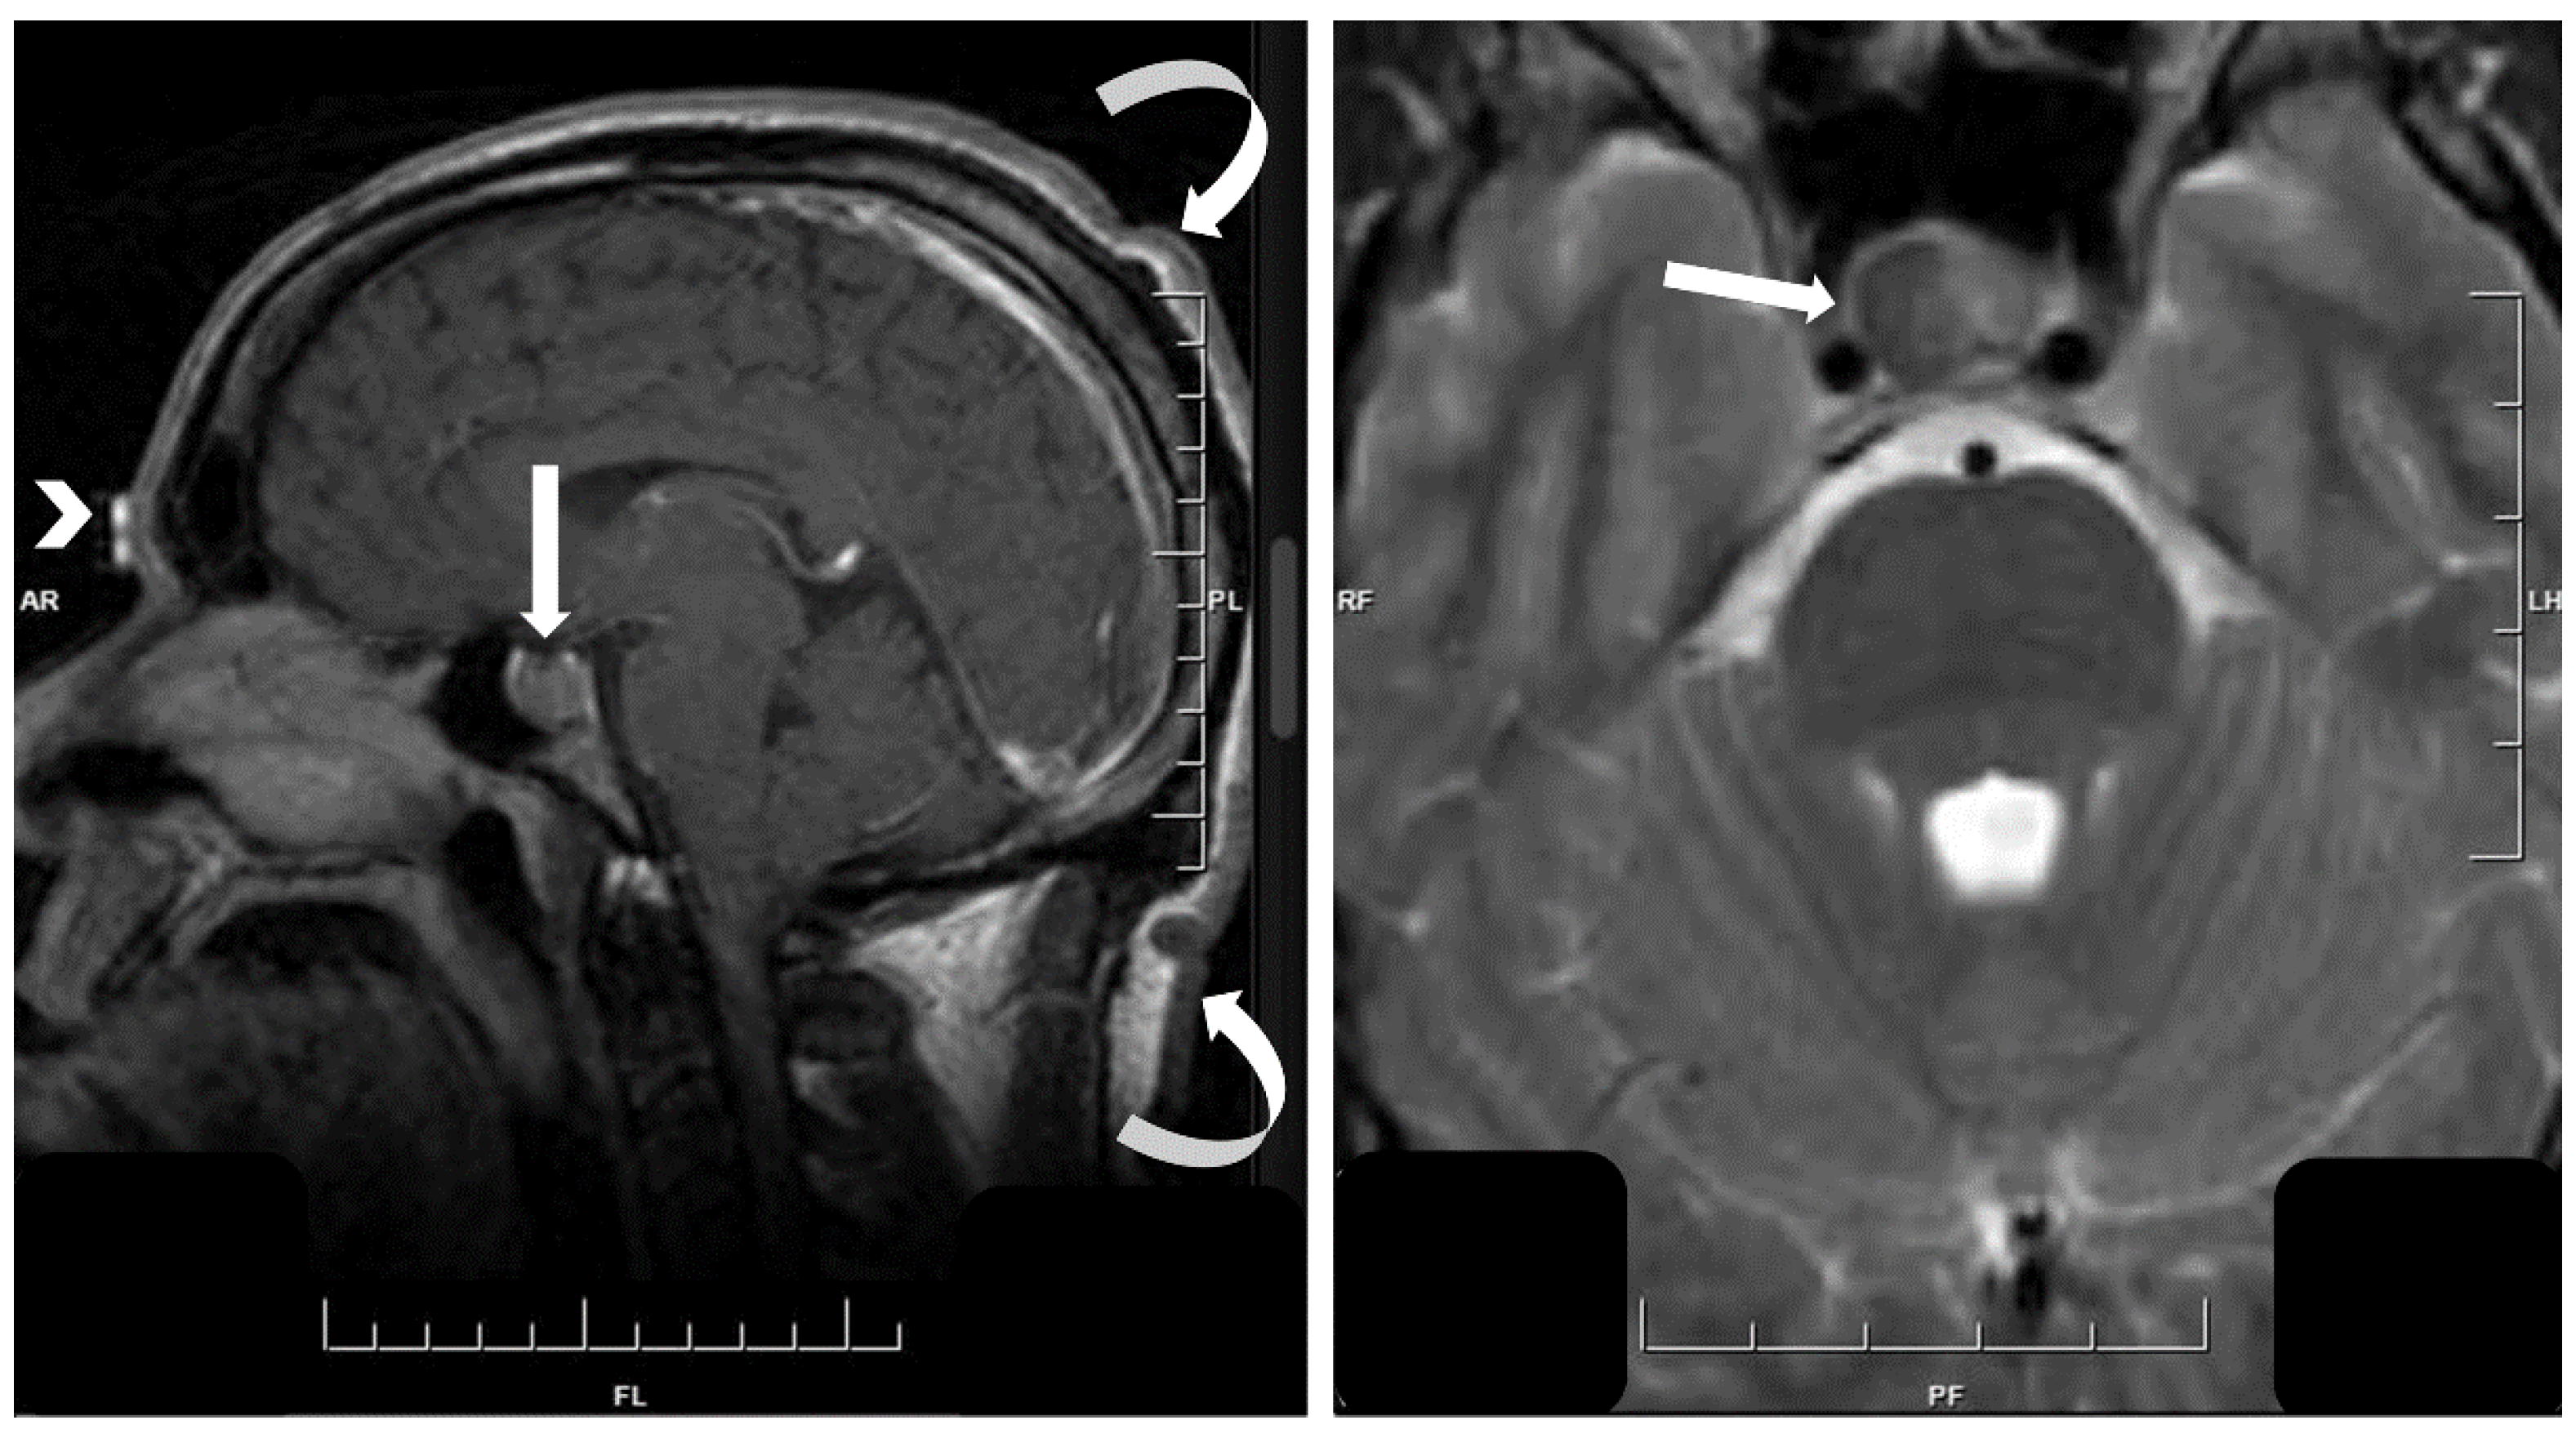

- Asa, S.L.; Kucharczyk, W.; Ezzat, S. Pituitary acromegaly: Not one disease. Endocr. Relat. Cancer 2017, 24, C1–C4. [Google Scholar] [CrossRef] [PubMed]

- Heck, A.; Ringstad, G.; Fougner, S.L.; Casar-Borota, O.; Nome, T.; Ramm-Pettersen, J.; Bollerslev, J. Intensity of pituitary adenoma on T2-weighted magnetic resonance imaging predicts the response to octreotide treatment in newly diagnosed acromegaly. Clin. Endocrinol. (Oxf.) 2012, 77, 72–78. [Google Scholar] [CrossRef]

- Potorac, I.; Petrossians, P.; Daly, A.F.; Alexopoulou, O.; Borot, S.; Sahnoun-Fathallah, M.; Castinetti, F.; Devuyst, F.; Jaffrain-Rea, M.L.; Briet, C.; et al. T2-weighted MRI signal predicts hormone and tumor responses to somatostatin analogs in acromegaly. Endocr. Relat. Cancer 2016, 23, 871–881. [Google Scholar] [CrossRef] [PubMed]